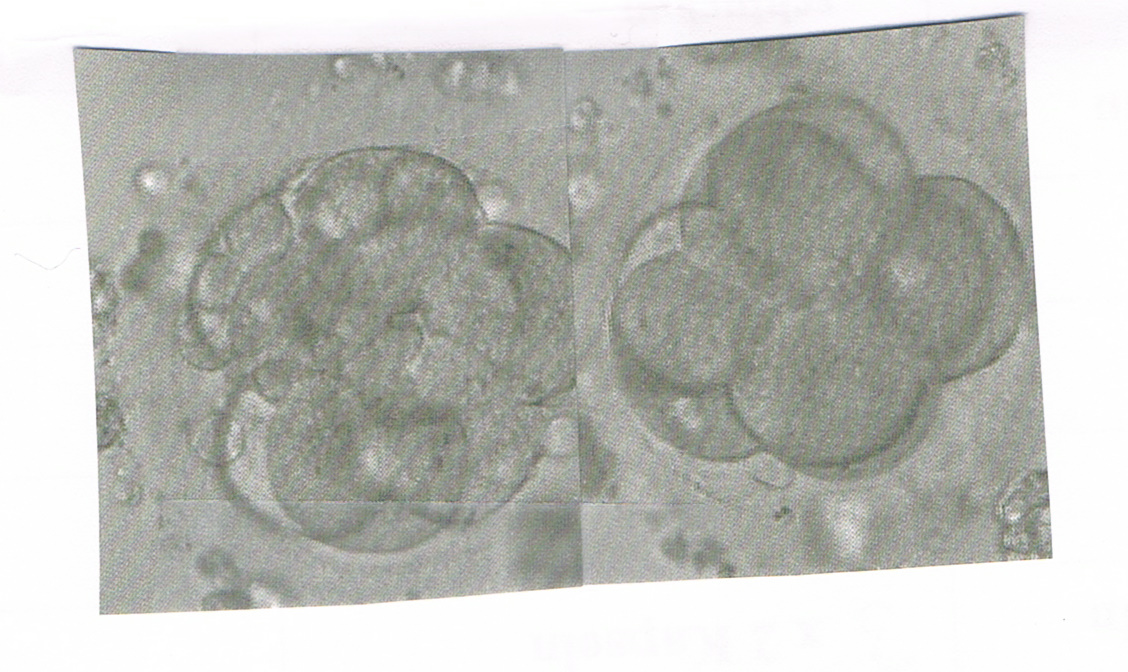

@ me: so nun habe ich 2 8-Zeller zurückgenommen nummer drei hatte bis dahin nur 5 zeller wird weiter beobachtet und soll am montag nachfragen was daraus geworden ist . die anderen beien sehen super aus ist einmal A und einmal B Qualität also dann

schaut mal wie schön .....